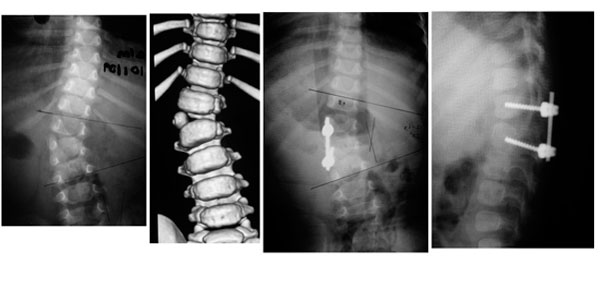

Paciente de 1 año y 8 meses con escoliosis congénita progresiva, se realizó resección de hemivertebra con colocación de tornillos transpediculares